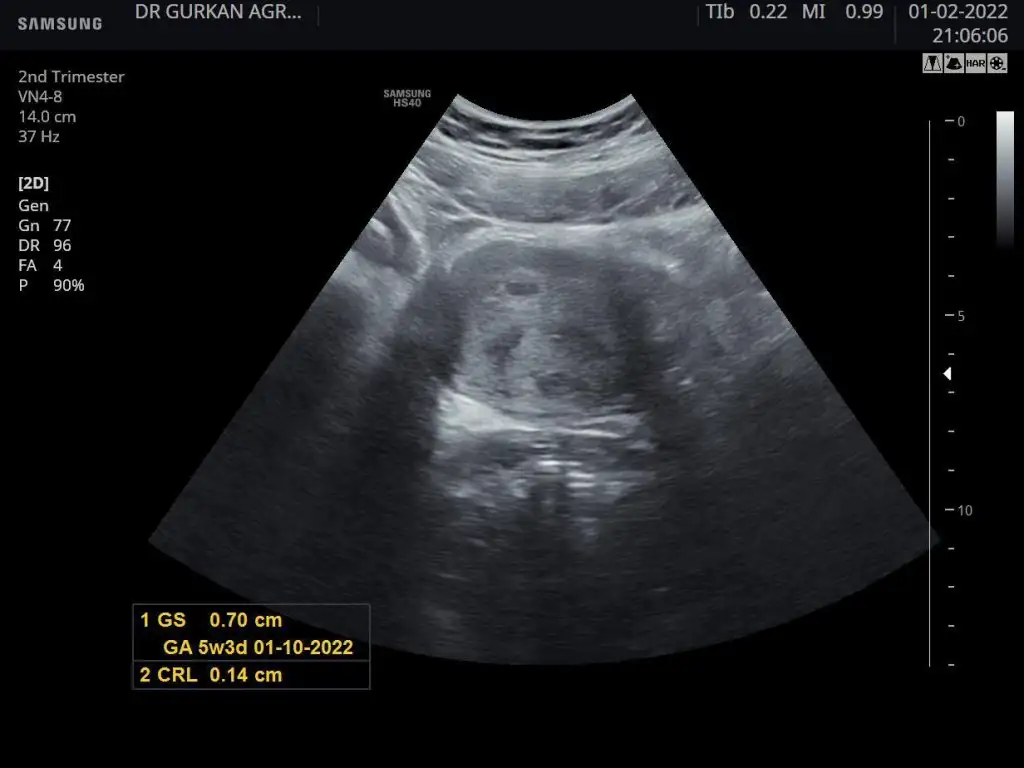

kız gibi duruyor kuzumMerhaba 12 haftalık, karından ultrason. Tahmininiz nedir :)

Burda keseye göre tahmin ettin değil mi canım .. bendekide soru bebek minnacık bişey orda nub görünmez hahahaNur topu gibi bir erkek bebeğiniz olacaktır inşallah :)